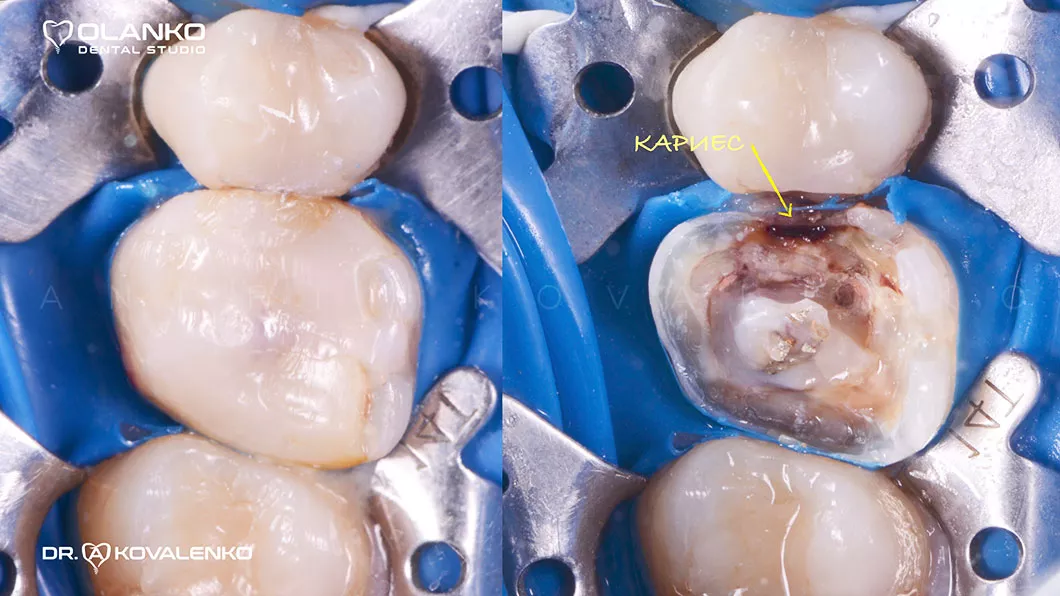

На сьогоднішній день, лікування зубів з використанням мікроскопу — це золотий стандарт світової стоматологічної практики. Складна система кореневих каналів має дуже малий діаметр та індивідуальну анатомію, тому лікар, який працює без збільшення, майже на дотик, не може якісно їх пролікувати.

Важливою перевагою Olanko dental studio (Оланко) м. Бровари є виконання всіх етапів лікування кореневих каналів тільки під контролем операційного дентального мікроскопу!

Ми маємо величезний клінічний досвід лікування зубів зі складною анатомією (викривленими, склерозованими каналами), а також повторного переліковування каналів з кістою, гранульомами, зламаними інструментами, з подальшими відмінними результатами загоєння хронічних запалень.